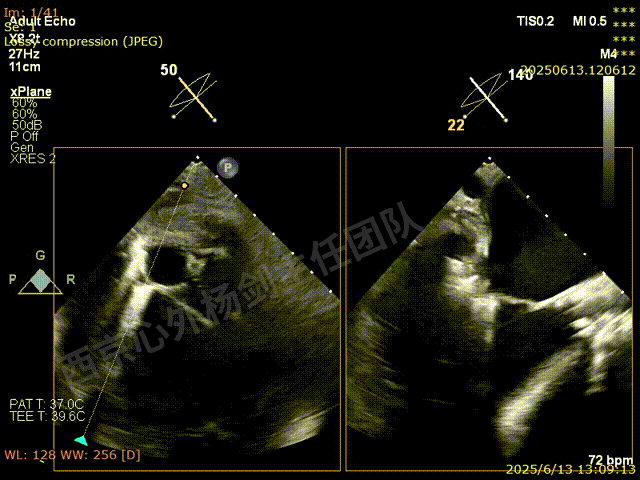

捕捞完成后确认orientation,gripper down

夹子关闭后检查夹子两侧反流

第一枚XTW释放后评估,外侧反流基本消失,内侧仍然有中度以上反流

第二枚XT于第一枚夹子内侧瓣上调整